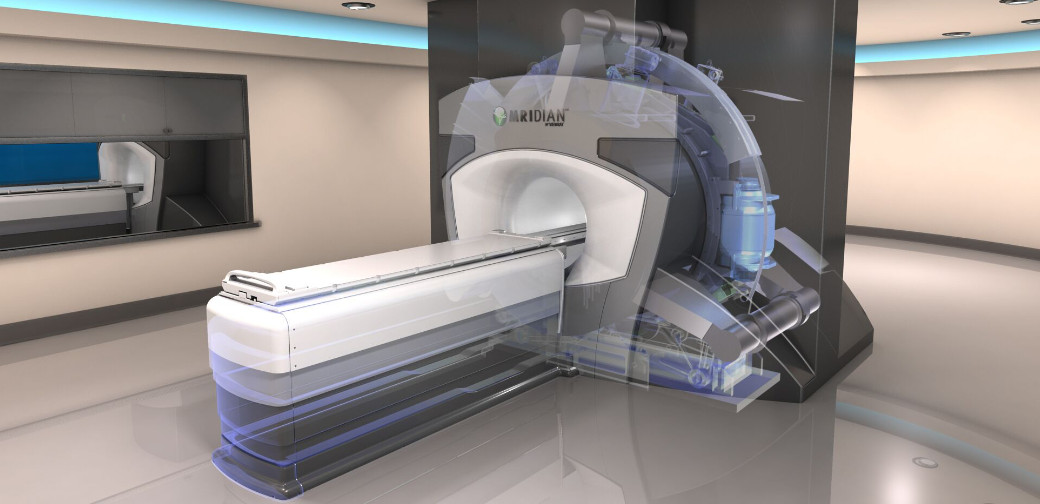

当院のMRIガイドIGRT治療器、MRIdian(ViewRay社製)は国立がん研究センター中央病院以降、国内では2台目、平成30年9月から当院で稼働しています。MRIdianの最も優れた特徴はMRI連速撮影によるリアルトラッキングです。(動体追跡照射法:迎撃法)。 図1の赤いターゲットの中に治療部位が納まった時だけ、自動的に照射がOnになり、ターゲットの枠から外れると自動的に照射がOffになります。 この技術により、肺がんや肝がんなど、動きが大きい腫瘍にもタイミングを合わせて照射することで、正常臓器への余分な被ばくを減らすことが可能になりました。

MRIdianのもうひとつの特徴は、MRI画像ベースで放射線治療を行うことです。

MRI撮影では放射線被ばくがなく、再撮影の負担も軽減されます。

さらにMRI画像は軟部組織のコントラストがよく、CT画像では難しい、肝、骨及び脳の病変を識別しやすい為、MRI画像を位置照合に用いることでより正確な放射線治療を実現しています。

バージョンアップ後は、治療時間の短縮が可能になります。

保険診療への適用も申請中です。

患者様へ寄り添う放射線治療にご期待下さい。